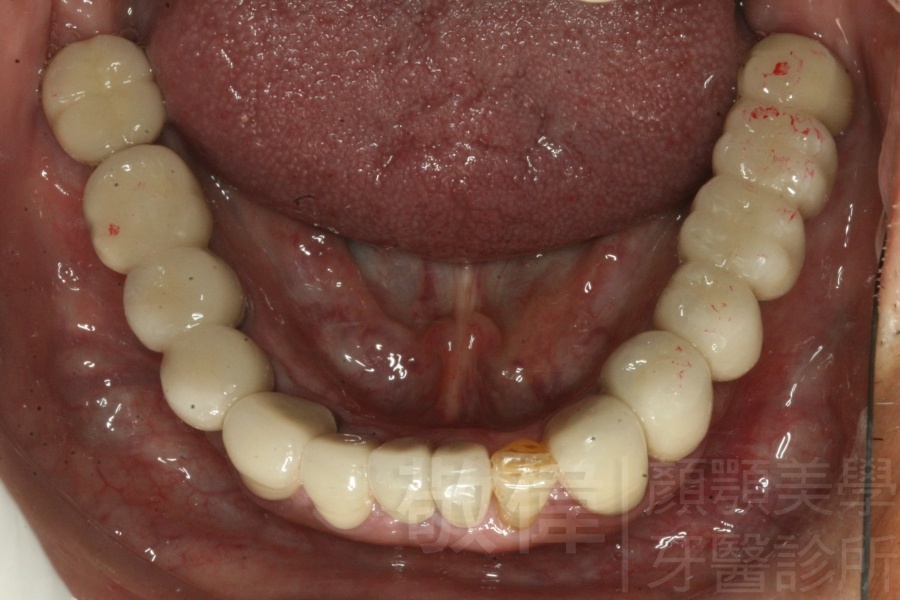

人工植牙/左下第1、2大臼齒植牙

治療前-下顎全口   治療後-下顎全口

治療前-缺牙區X光   治療後-大臼齒X光